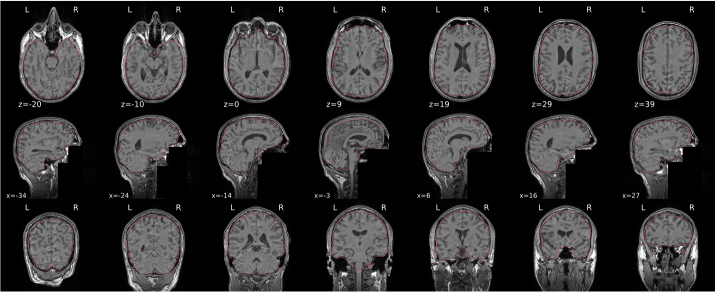

T1w skull stripping

Skull stripping is the process separating the brain (cortex and cerebellum) from the skull. The red line follows the outline of the brain and it separates it from the skull.

Example of a good subject

- There are no skull stripping errors, such as portions of the brain missing, or too much of the skull retained

- The red line follows the outline of the brain

Example of a bad subject

- There are skull stripping errors, such as portions of the brain missing, or too much of the skull retained

- NOTE: check all the images (slices) in the report. If only one image (slice) looks problematic, it is possible that the subject is okay and it is just a visual issue in that particular screenshot

Summary

| Good | Bad |

|---|---|

| The brain is fully inside the red line | Structures like the cranium or the eyes are inside the red line |

| No important brain structures are outside of the red line red line follows the natural outline of the brain | Important brain structures are missing inside of the red line |

-> if only one slice is problematic, it could be an issue related to the visual depiction of the data instead of an issue related to the test subject